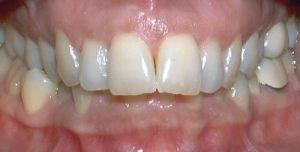

Spacing

Spacing problems may be caused by missing teeth, or they may only be a cosmetic or aesthetic issue.